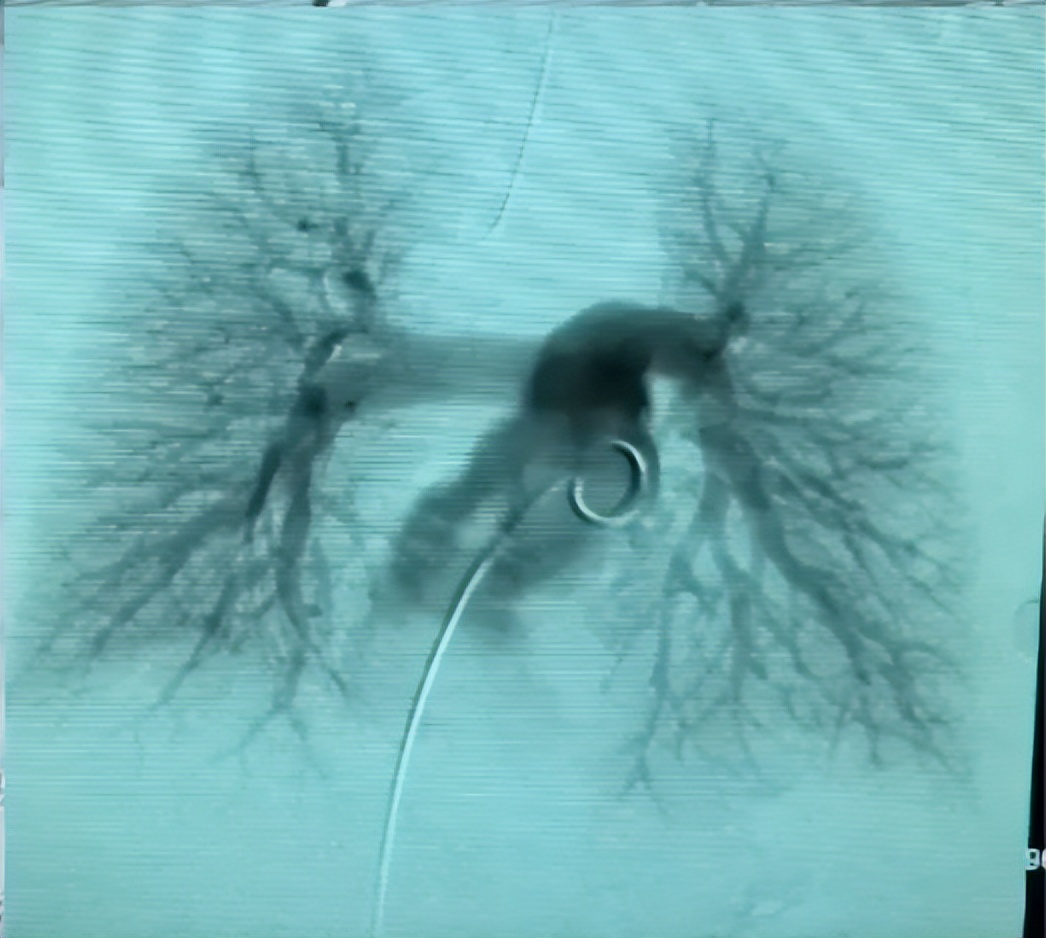

术中发现断裂的PICC导管(箭头示)漂浮至右侧肺下动脉远端,一端飘浮在肺动脉干。

术中采用经皮血管内利用抓捕器抓捕住导管近端,轻柔拖拽导管,将断裂导管取出。